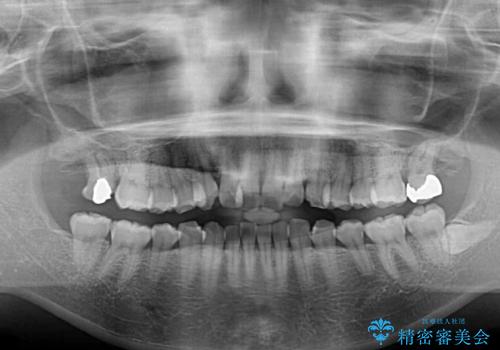

- 奥歯の咬み合わせと治療を放置したまま奥歯を気にして来院された患者様です。

上顎骨の幅が下顎骨よりも小さいので、拡大装置により骨幅を広げて上下関係を改善し、その後インビザラインにて歯並びを整えることとしました。

矯正治療後には土台のままとなっている歯をセラミッククラウンにて補綴治療を行うこととしました。

上下の骨幅を改善したことで、スムーズに歯列矯正を行うことができました。

土台のまま放置されていた歯は土台の状態で咬み合っていましたが、急速拡大を行った際に咬み合わせが著しく挙上されたため、その際に土台を大きくすることで咬み合う歯との距離を確保しました。